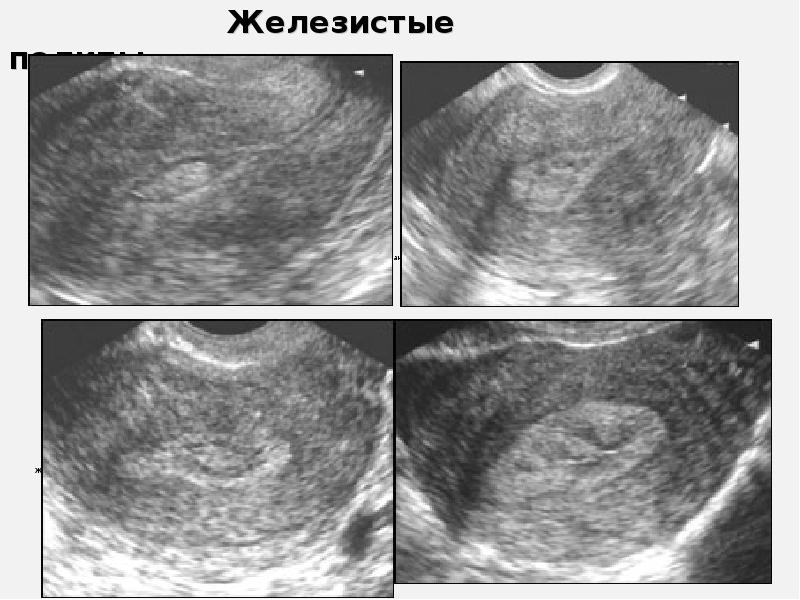

Раздел: Кадры перемен